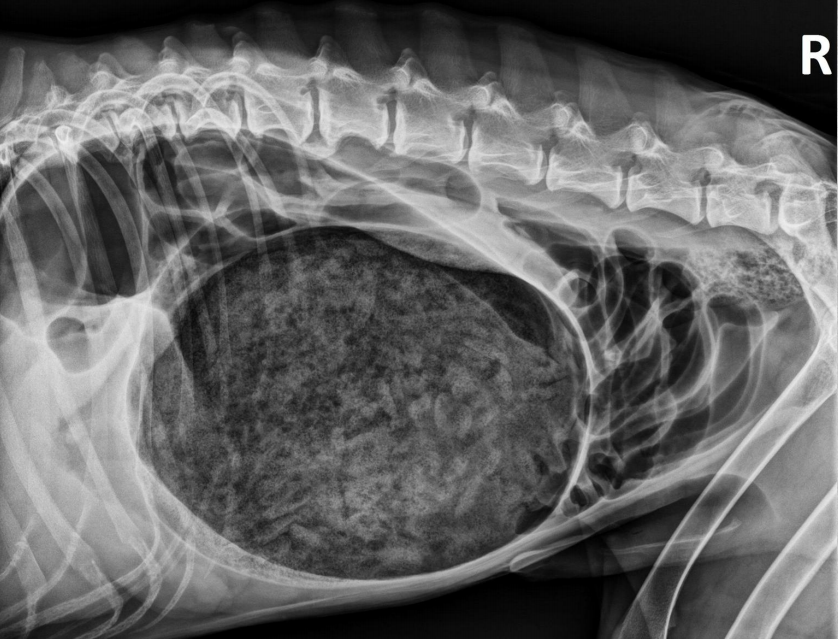

15 yo cat

Weight loss, anorexia, vomiting

Findings:

● Dilated bowel filled with fecal mass

– Not only large intestine, but small

intestine as well.

● Megacolon